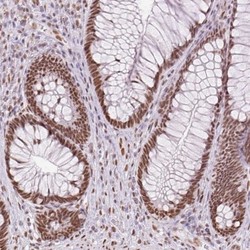

- Immunohistochemistry: ZFR2 Antibody [NBP2-38766] - Staining of human rectum shows strong nuclear positivity in glandular cells.